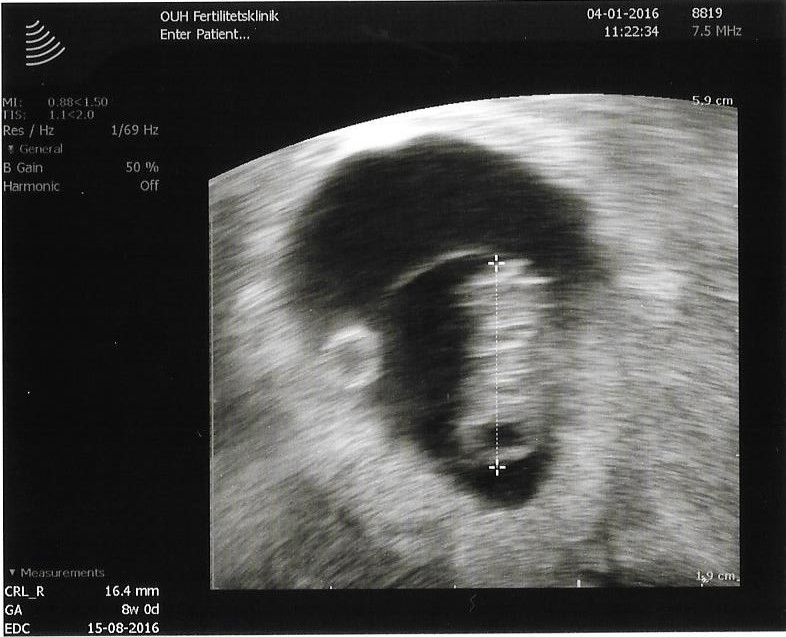

Var idag inde og få lavet en tidlig skanning og alt så heldigvis fint ud, det var dejligt at se det lille hjerte slå

Vedhæftede fotos (klik for at se i fuld størrelse)

Jeg er 8+2 nu, i mandags da jeg fik scanningen var jeg 8+0

Godt nok et fint billede..mine er grumsede og man kan lige ane noget der ligner en baby..